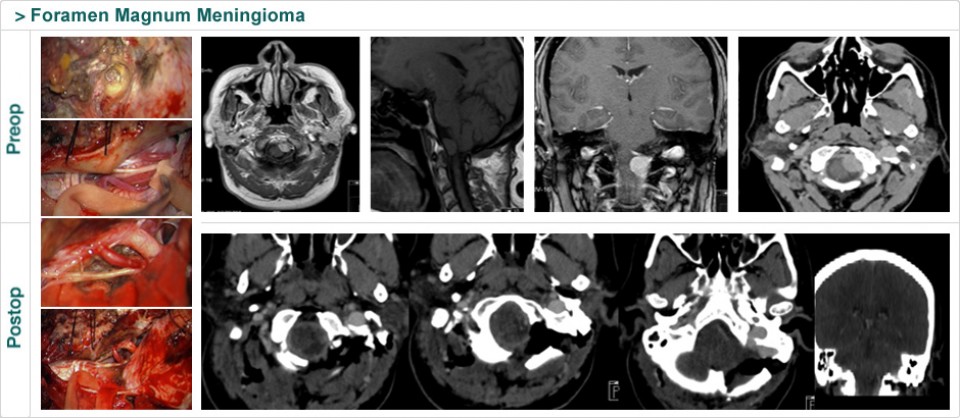

Dr. Attia is an attending neurosurgeon and the director of skull base surgery service in the department of neurosurgery at Sheba Medical Center in Tel HaShomer. His specialty focuses on skull base and cerebrovascular neurosurgery.